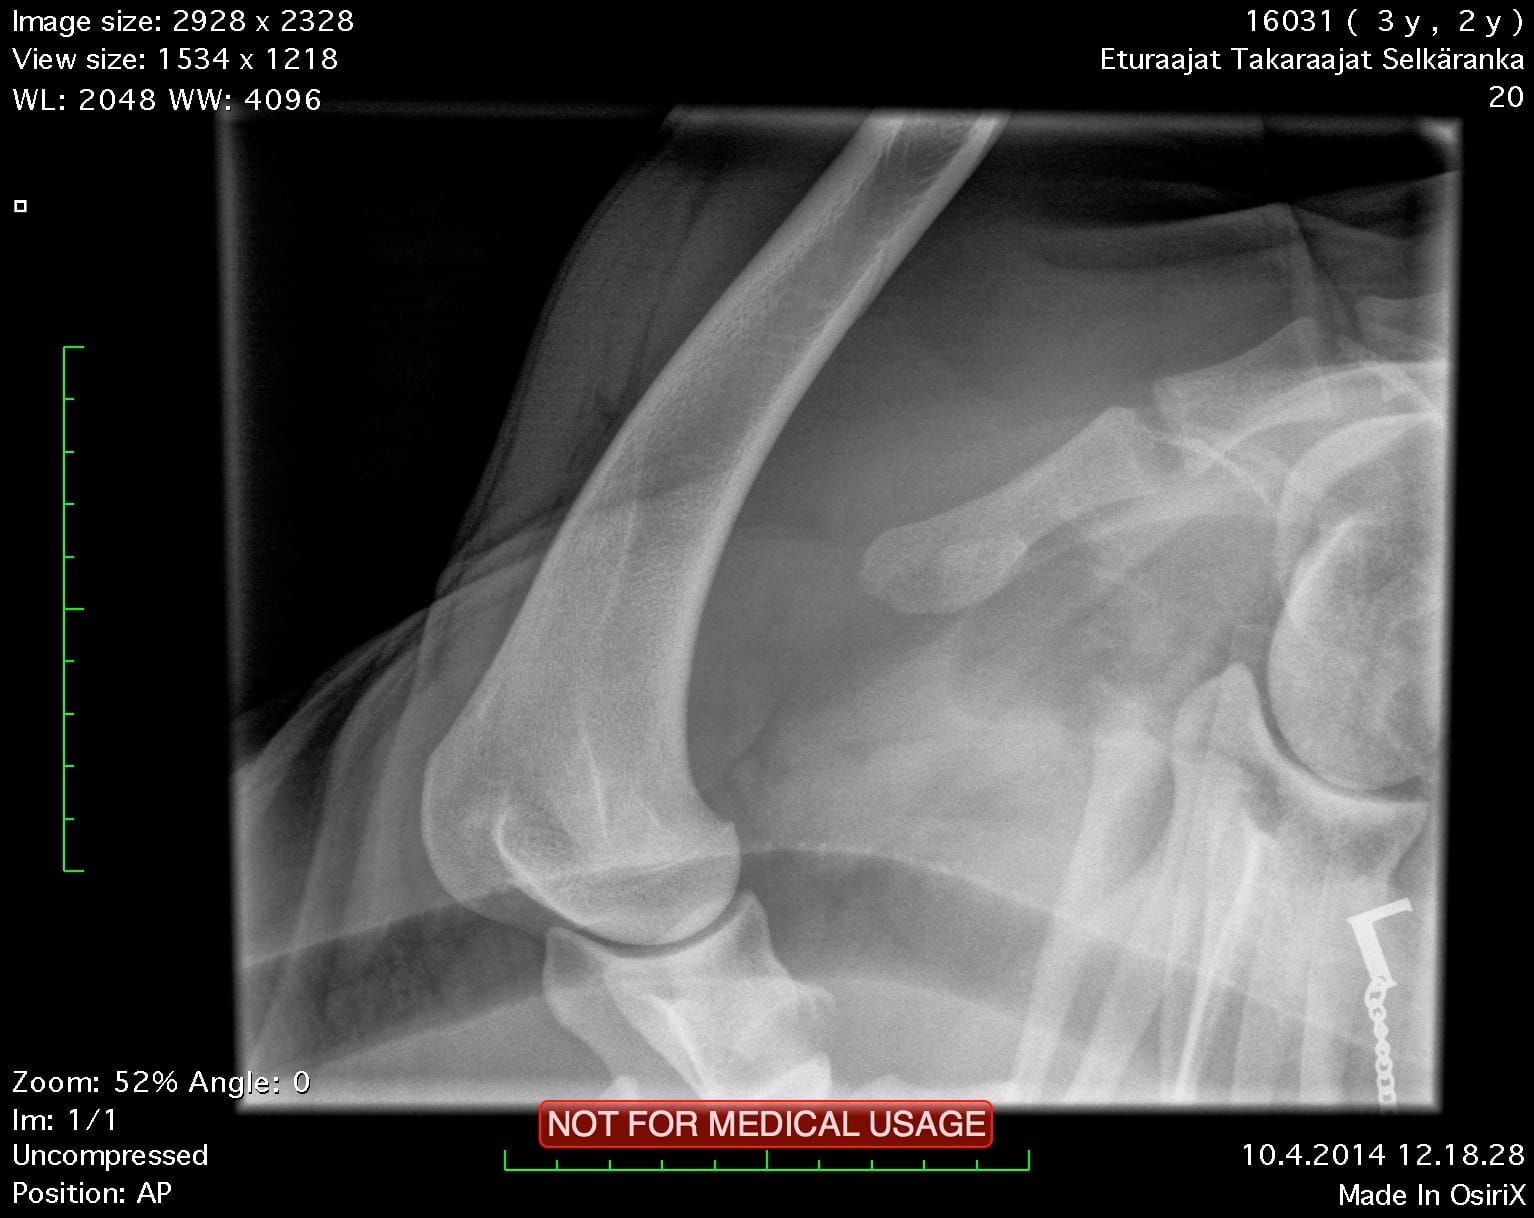

| Shoulders: | clear | |

| Spine: | SP0, LTV4 (8 lumbosacral vertebrae) | |